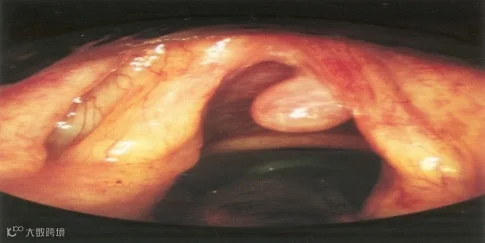

喉的良性增生性病变:如声带小结、声带息肉、声带囊肿等,患者声嘶多呈持续性。

喉乳头状瘤:患者病程缓慢,声嘶逐渐加重,检查可见灰白色乳头样肿瘤,常见于声带或室带处。易复发,可癌变。